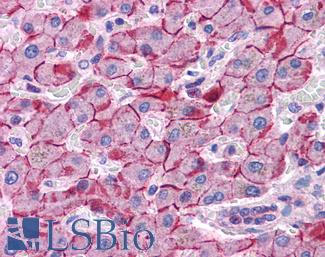

Anti-E Cadherin antibody IHC of human liver. Immunohistochemistry of formalin-fixed, paraffin-embedded tissue after heat-induced antigen retrieval. Antibody LS-B4674 concentration 5 ug/ml. This image was taken for the unconjugated form of this product. Other forms have not been tested.

E-Cadherin (CDH1)